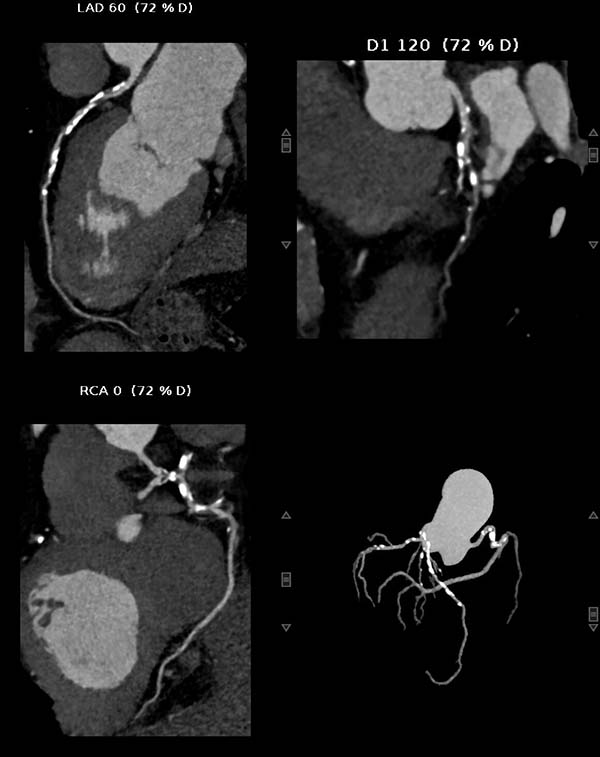

重度钙化的冠状动脉(MIP图像)、黑色部分为钙化斑块

重度钙化的冠状动脉(CPR图像)

冠状动脉钙化积分>1500,提示极重度钙化